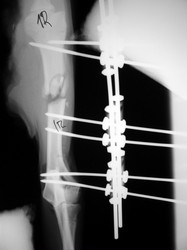

PRÁCTICAS CURSO DE FIJACIÓN EXTERNA PERFECCIONAMIENTO.

Húmero.